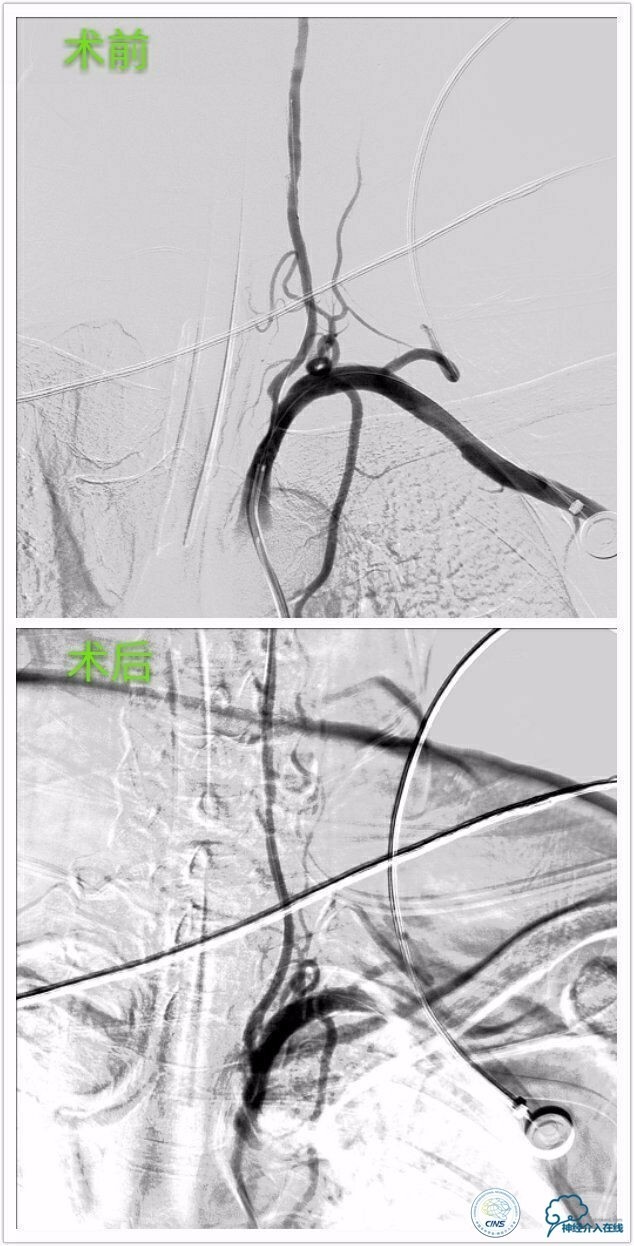

行左侧颈内交通段、左椎开口支架成形术治疗。

》左侧颈内交通段球囊扩张支架成形术:

》左侧椎动脉开口球囊扩张支架成形术: